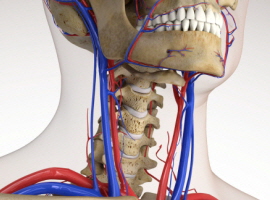

목디스크 환자 10%가 알게되는 목디스크 증상으로 이명, 어지럼증, 현기증, 두통이고요. 그리고 목과 결부된 경추 신경이 자극을 받아 생기는 현상입니다. 때문에 빈번히 좋지않은 자세로 긴 시간동안 독서, 스마트폰, 컴퓨터 등을 하여 거북목 증상을 겪는 경우 빈번히 생겨난다고 하더라고요. 고로 두통의 경우 목에서 뇌로 상승해는 혈관 및 신경이 압박되어 순조로운 순환이 되지 않으니 일어난다고 하고요.

목디스크 증상 4번째는 이명이고요 목디스크 환자의 10퍼센트크기가 두통과 같이 이명을 앓고 있습니다. 이러한 목디스크 증상들이 출현하는 이유는 목과 맞닿은 경추 신경이 자극을 받기 때문이고요. 연속으로 해로운 자세로 한동안 PC를 하거나아니라면 독서, 스마트폰 등을 하다가 보면 거북목이 이유가 되는 것이 되어 수면장애와 이명이 생겨나게 된다고 합니다. 특별히두통의 경우 목에서 뇌로 향하는 혈관과 신경이 압박되어 거침없는 순환이 되지 않도록해서 생기게 되고 산소 결핍 현상이 발생하는 것으로 증상이 나타난 것이라고 해서 빠른 치료가 필요하고요.